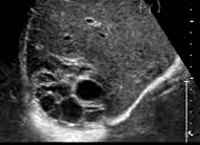

K77.0 Поражения печени при инфекционных и паразитарных болезнях, классифицированных в других рубриках